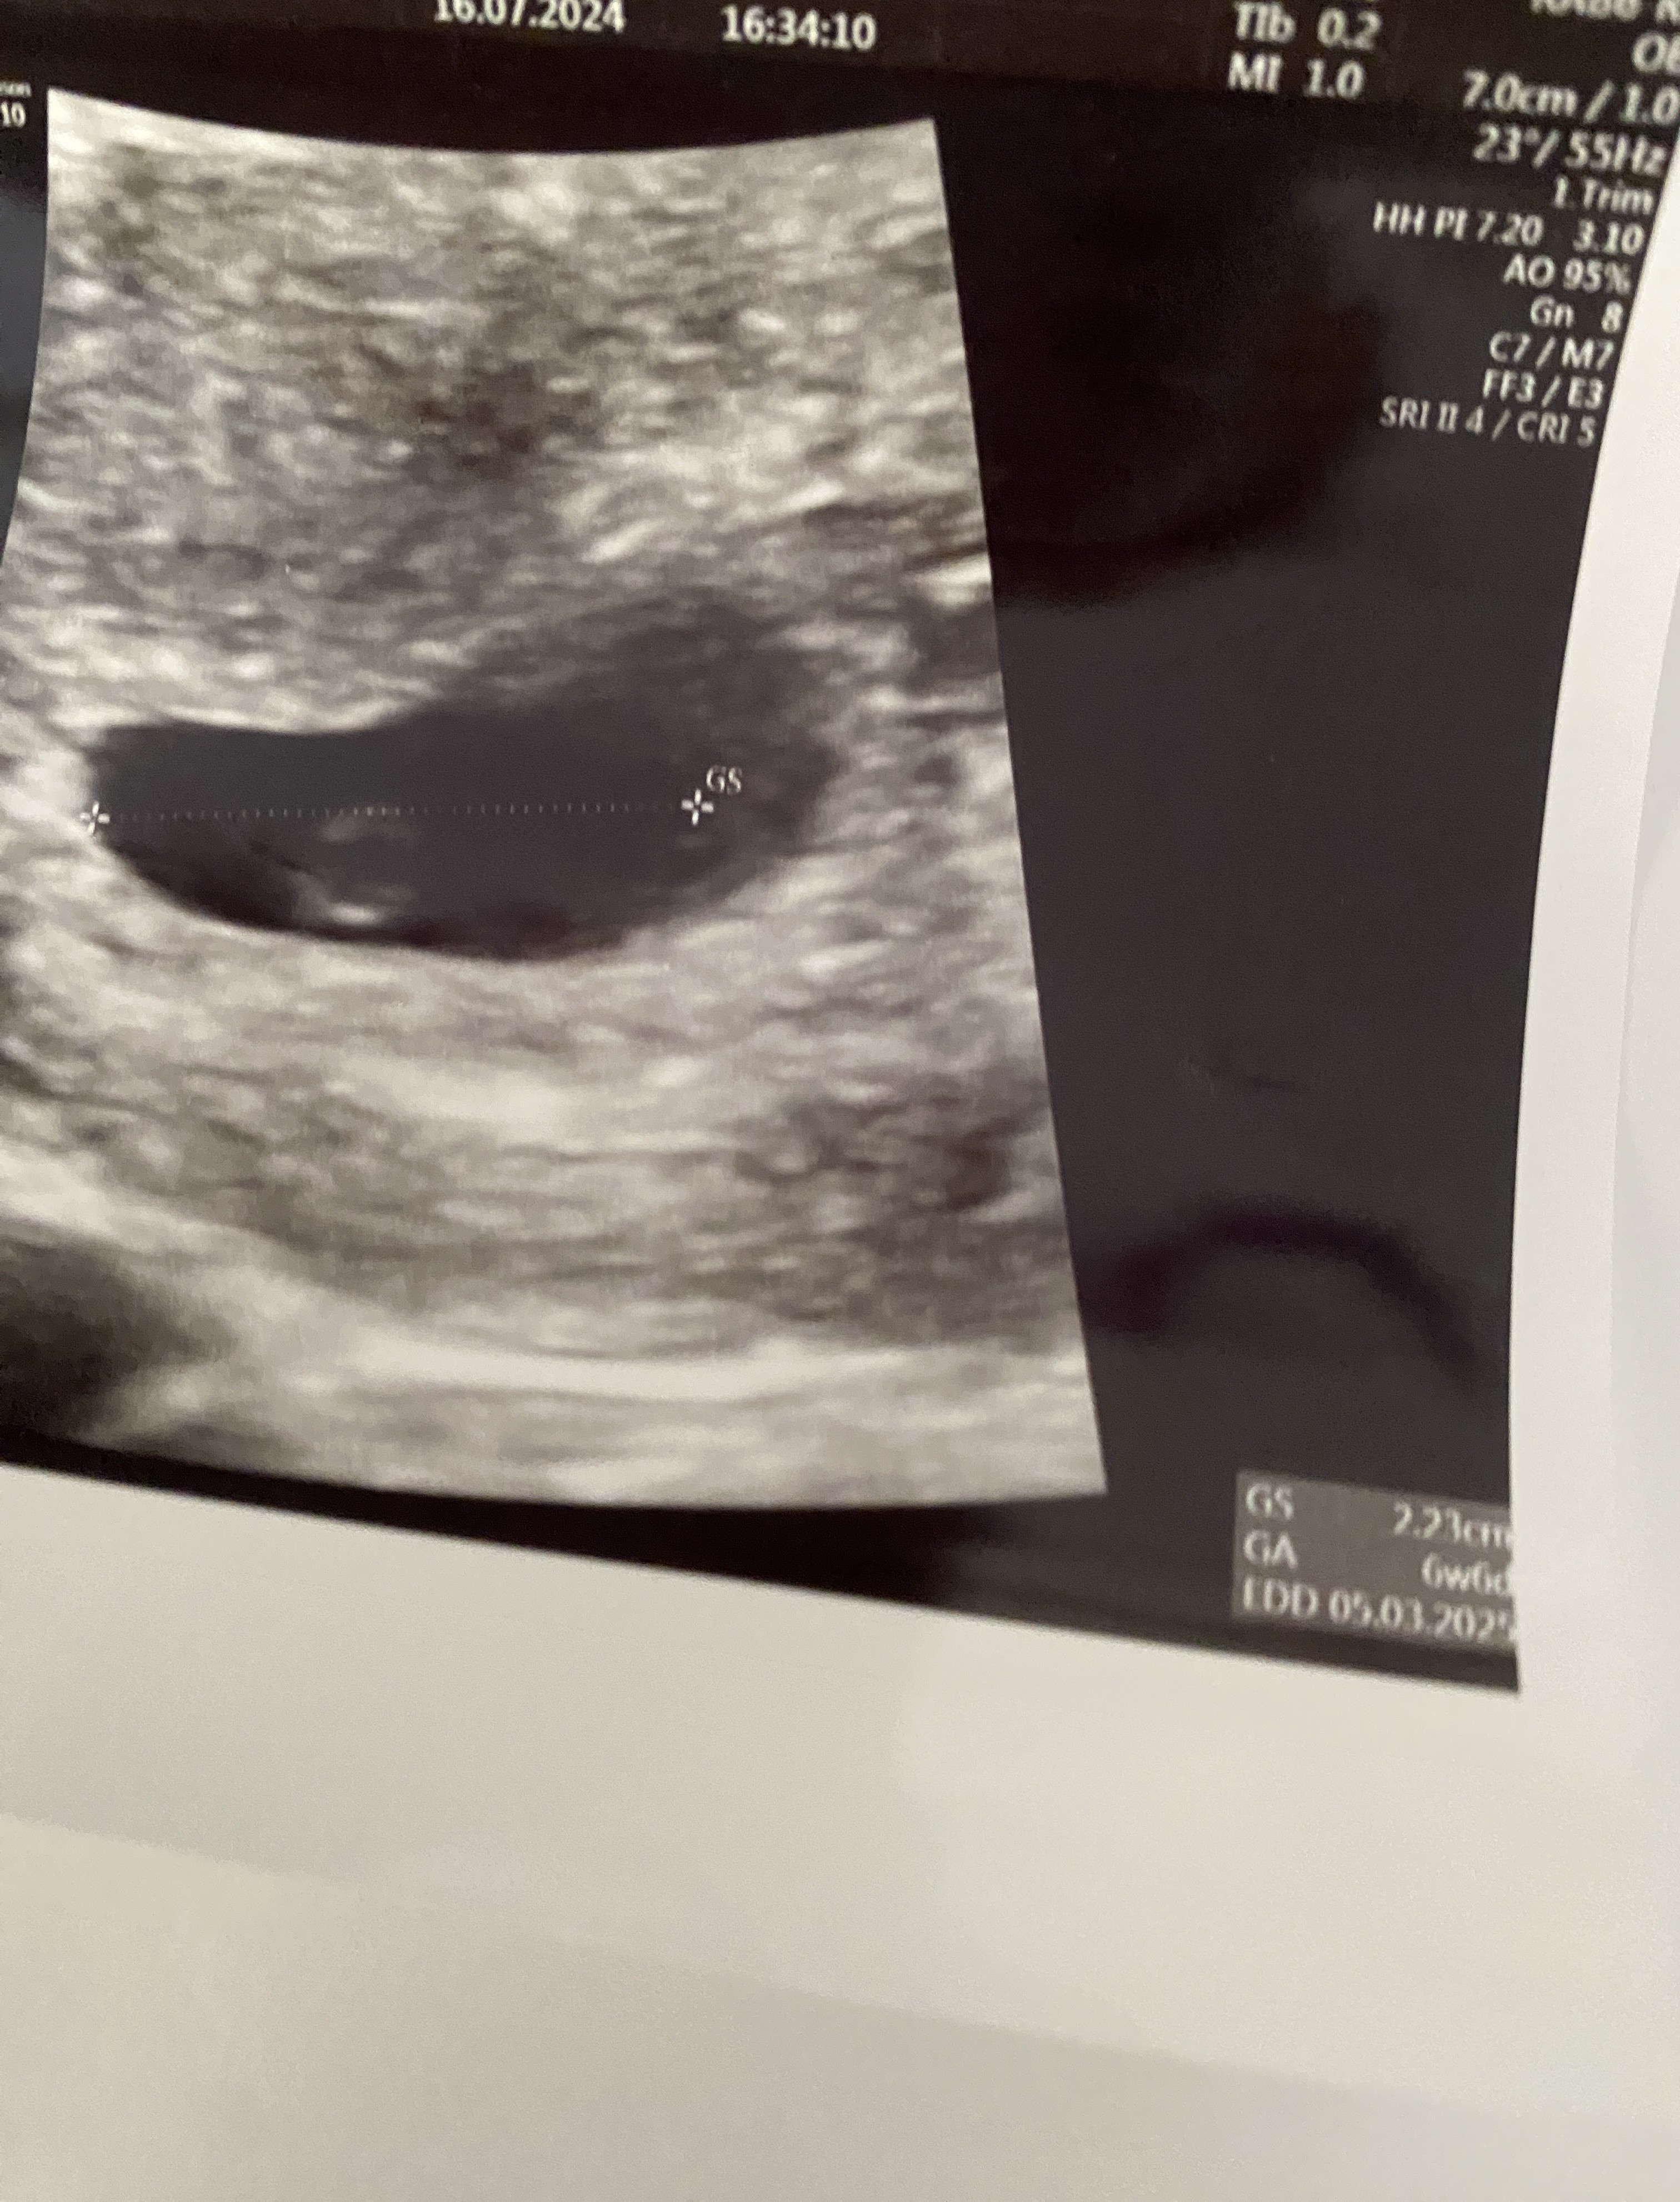

Hej , ost miesiączka 6 czerwca , jestem w ciąży dwa tygodnie temu według usg ciąża mi wychodziła starsza i termin na usg to 5 marca i 6+6 a po dwóch tygodniach na wizycie termin na USG pokazuje 16.03 i 7+2 ale serduszko bije . Zaznaczę Że poprzednią ciążę poronilam w 8 tyg a tera też mam brązowe plamienia . Lekarz pow że na ten moment wszystko ok ale mi się nie wydaje …. Ktoś miał podobny przypadek ?

Ale 1 usg to zapewne pęcherzyk a 2 to już zmierzony zarodek wieć nie ma co tych wartości porównywać. Moim zdaniem kiepsko to wygląda,że przez 2 tygodnie ciąża ma ten sam wiek. Nie mniej jednak wiek pokrywa się z ostatnim dniem miesiączki, więc może rzeczywiście ten pierwszy pomiar i wyliczenia są błędne.